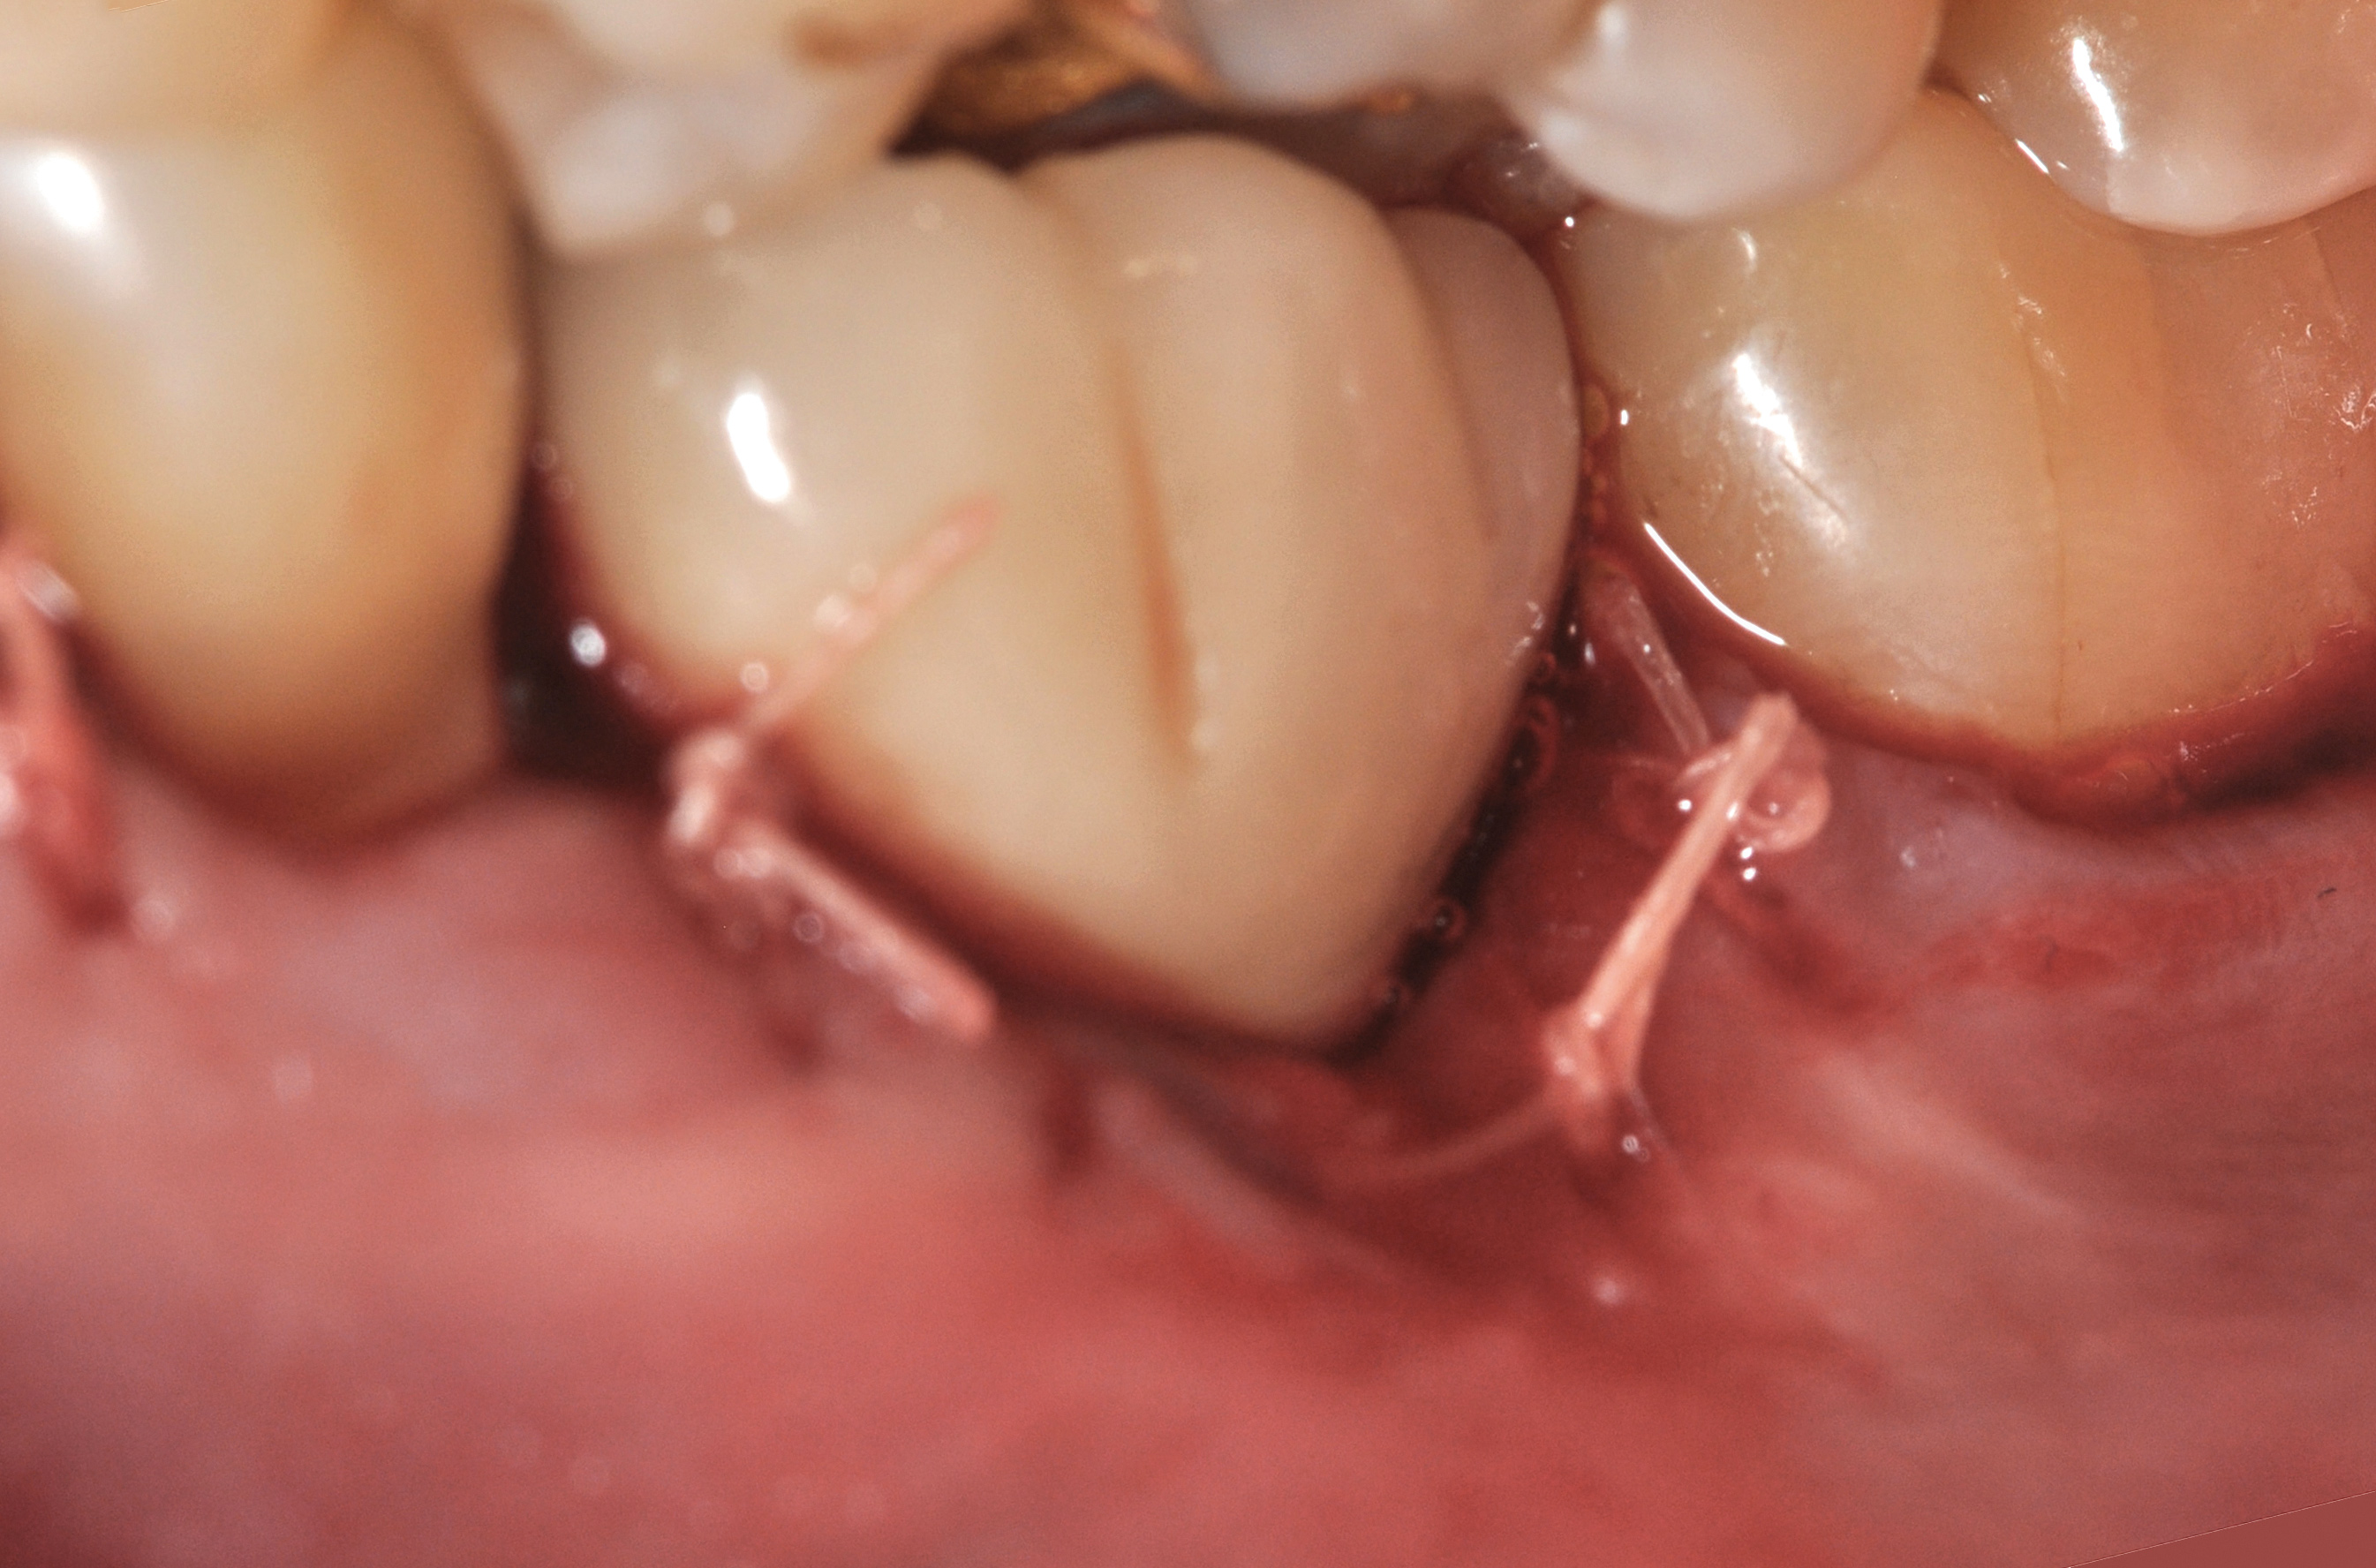

Fig 18. A full-thickness flap from teeth Nos. 18 to 20 revealed granulomatous tissue in the circumferential defect around implant No. 19.

Figure 18

Fig 19. The circumferential defect was debrided. Note excess cement extending apically from the margin of the crown into the defect; residual cement has been shown to be complicit in the development of peri-implant disease.

Figure 19

Clinical examination showed 2 mm of buccal recession with a shallow vestibule and absence of keratinized attached gingiva against the crown with 8 mm of circumferential pocketing accompanied by bleeding upon probing (Figure 15 and Figure 16). A periapical radiograph showed a symmetrical vertical osseous defect causing the loss of 50% of the bone around the implant (Figure 17). Because the patient had made a significant investment of time and finances to replace her lost tooth with the implant, she desired that the implant and restoration be retained, if feasible.

A surgical flap procedure was performed with the intent of thoroughly debriding the granulomatous tissue from the osseous defect (Figure 18 and Figure 19), mechanically and chemically detoxifying the surface of the implant (Figure 20 through Figure 22), and grafting the infrabony component of lesion with bone xenograft (Bio-Oss®, Geistlich Pharma, www.geistlich-na.com) in an attempt to reduce the vertical defect (Figure 23). To concurrently resolve the mucogingival problem, the plan called for placing a dermal allograft (Dermis Allograft, DENTSPLY International, www.dentsply.com) on the buccal (Figure 24) and then replacing the flap (Figure 25).